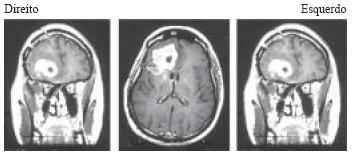

As imagens de RNM, com seqüências ponderadas em T1, feitas com contraste gadolíneo, mostram a presença de um processo expansivo na região frontal direita.

O achado anátomo- patológico mais relacionado à piora do prognóstico do tumor apresentado é

Menino de 9 anos de idade apresenta-se com transtorno progressivo de marcha, oligocinesia, movimentos distônicos dos membros superiores, declínio cognitivo e progressiva diminuição da visão. Ao exame clínico, constata-se hipertonia generalizada nos 4 membros e discreta hiperreflexia. Sua ressonância nuclear magnética de crânio mostra a alteração regsitrada na figura:

Corte coronário de RNM com imagens ponderadas em T2 Pode-se afirmar que o metal acumulado de forma significativa no sistema nervoso central do paciente é o